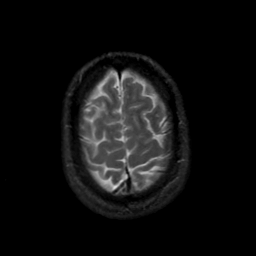

MR Study #18, July 21, 1991 -- Slice #43

[Home][Help][Clinical][Tour 1][Tour 2] Slice 43